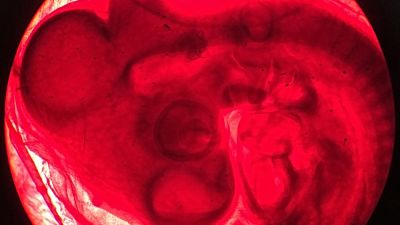

"I knew this was something that’s going to trickle down to the rest of us," said Coyne. She uses the placenta, which people may not think of as fetal tissue but technically is classified as such because the fetus produced it, to study how viruses such as Zika get past that protective barrier early in pregnancy.

Zika offers a glimpse at the difficulty. Somehow, the Zika virus can sneak from the mother’s bloodstream across the placenta, which protects and nourishes the fetus, and target the fetus' brain. It’s something researchers hope to learn to block.

Studying the placentas of small animals or even monkeys isn’t a substitute because they differ from the human organ, said Emory University researcher Mehul Suthar. For example, the specific type of placental cell where Zika can lurk in humans isn’t thought to be present in mouse placentas.

And because the placenta continually changes as the fetus that created it grows, first-trimester tissue may show a very different vulnerability than a placenta that’s expelled during full-term birth, when it’s no longer defined as fetal tissue but as medical waste.